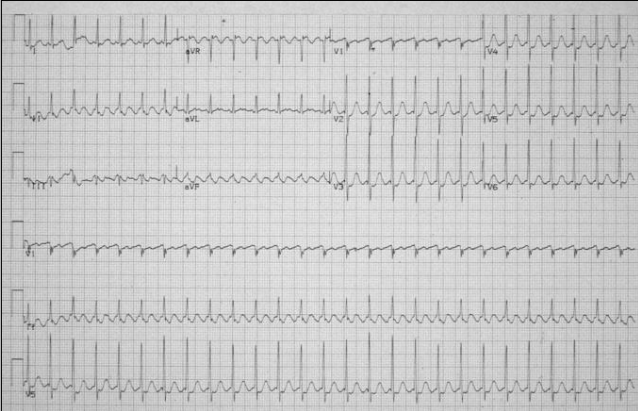

What is this?

Atrial flutter